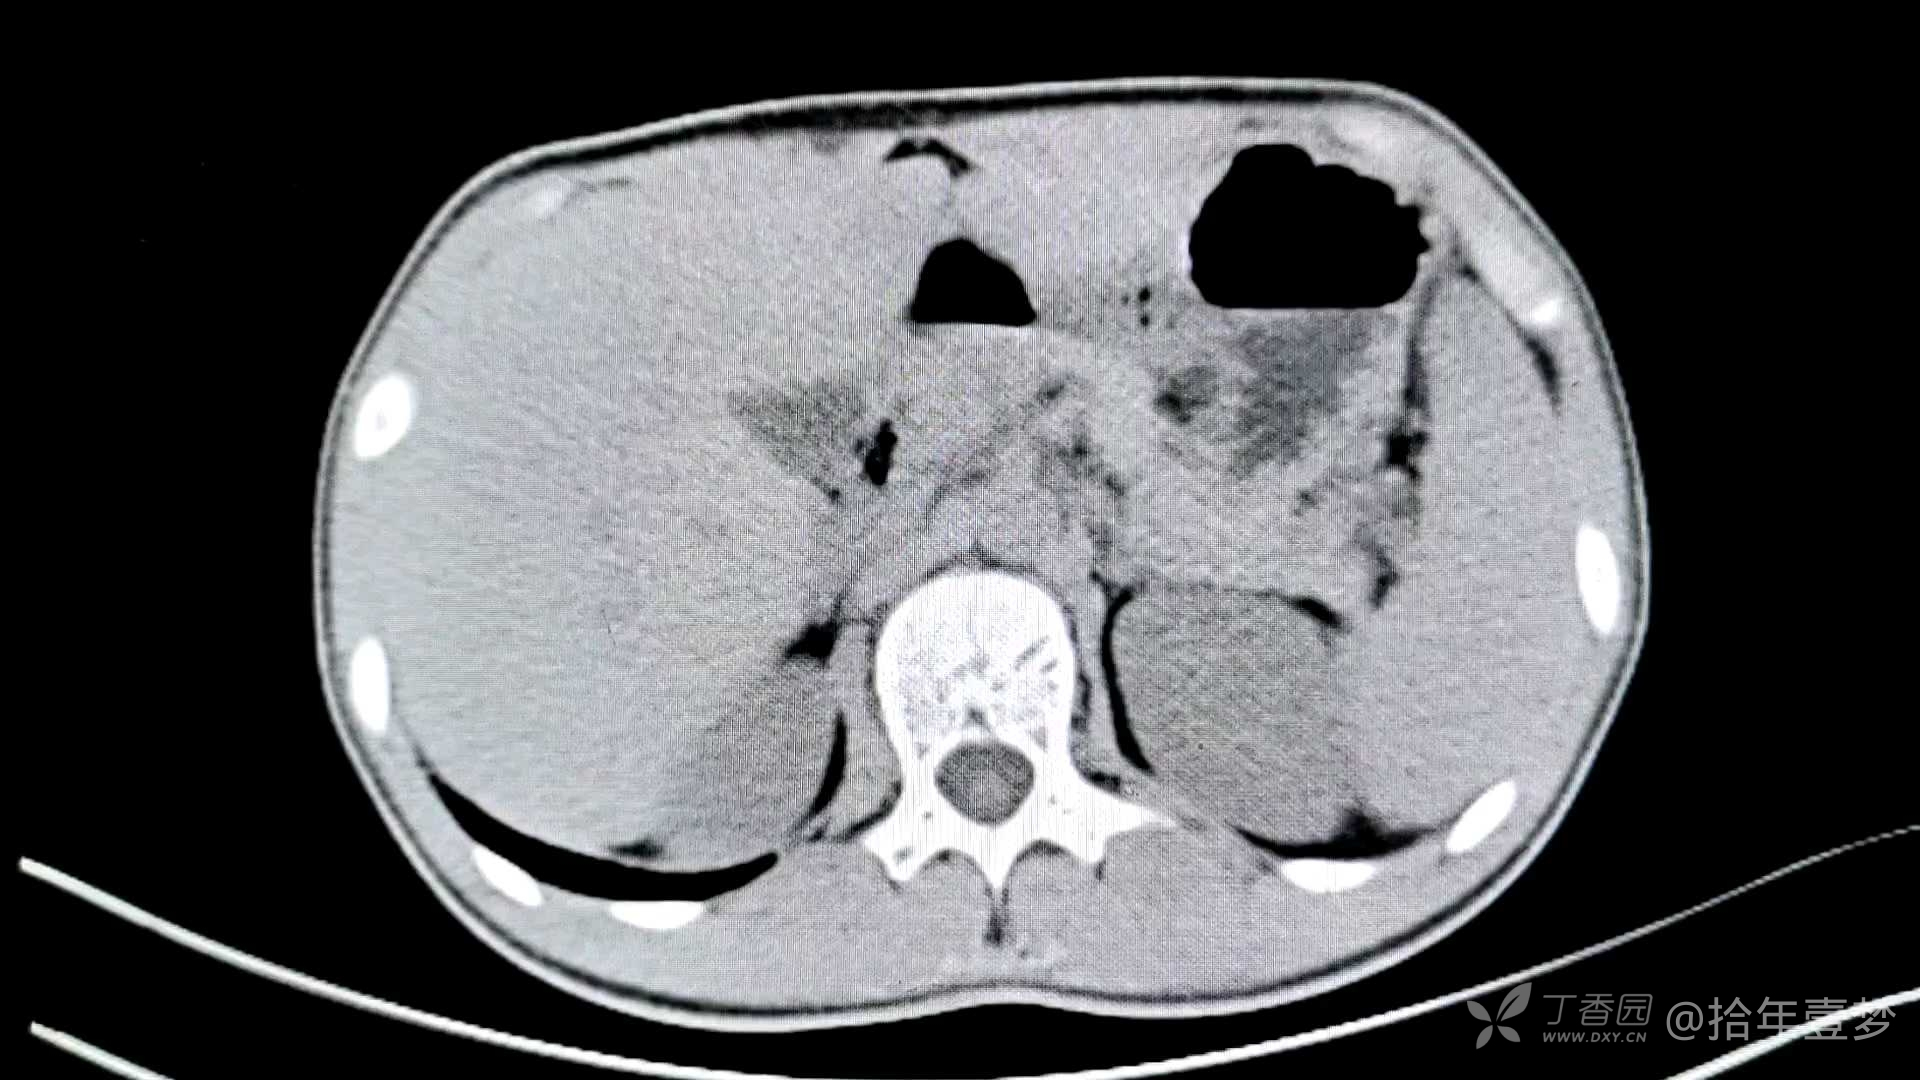

辅助检查如下

诊断:完全性肠梗阻。